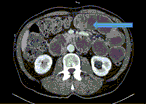

Infiltrating caecal carcinoma versus appendicitis with caecal phlegmon—can computer tomography differentiate them?

Henry To and others

Journal of Surgical Case Reports, Volume 2017, Issue 2, February 2017, rjx006, https://doi.org/10.1093/jscr/rjx006